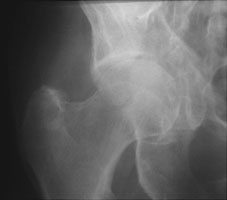

- Click on the image for a larger versionBAxial CT. This demonstrates a fracture of the neck of the femur and the anterior column of the acetabulum.